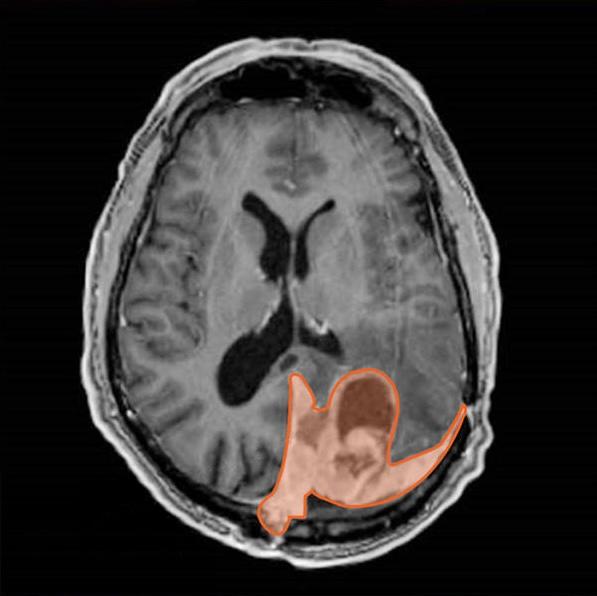

脑膜瘤患者的影像扫描(橙色)。研究人员开发了一种基因表达特征,可以帮助为患有这种脑癌的人制定治疗决策。